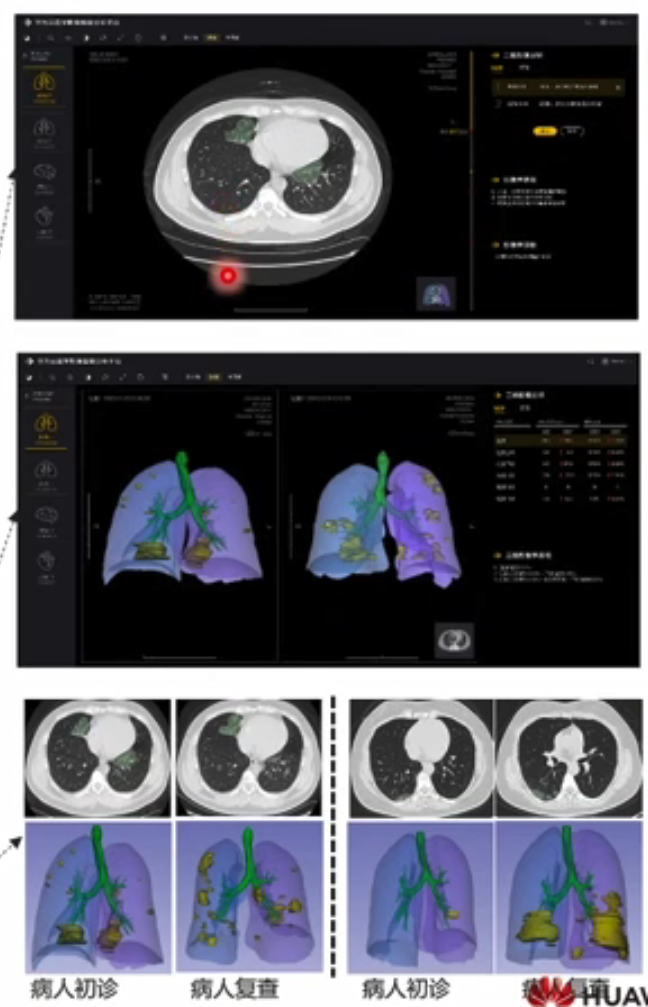

第一步:病灶分割与定量分析

1. 检出磨玻璃密度影(GGO)、实变密度影等病灶及其影像位置;

2. 自动测量病灶的体积。

第二步:3D重建

1. 输出病灶的解剖定位,具体到左右肺;

2. 自动进行三维立体重建,直观呈现结果。

第三步:对比分析

1. 清晰对比初诊及经过治疗后的复查情况,方便指导病人用药治疗。